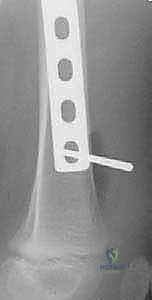

Finally, the distal femoral physis represents a critical "no-go" zone. The distal extent of the plate and the trajectory of the most distal screws must be meticulously planned and fluoroscopically verified to ensure they remain strictly epiphyseal/metaphyseal and do not violate the undulating distal growth plate. Iatrogenic physeal arrest in the distal femur is a devastating complication that can result in profound angular deformity and leg length discrepancy, given that the distal femur contributes approximately 70% of the longitudinal growth of the entire femur.

Meticulous preoperative planning differentiates a smooth, efficient surgery from an intraoperative struggle. The first decision is plate selection. For the vast majority of pediatric femoral shaft fractures, a 4.5-mm narrow LC-DCP provides optimal strength and a favorable biological profile. If the bone is osteopenic, or if the fracture is highly proximal or distal necessitating enhanced angular stability, a 4.5-mm narrow LCP (locking compression plate) is selected. The plate must be long enough to span the entire fracture zone while allowing for adequate fixation proximally and distally. The standard "rule of sixes" applies: aim for a plate long enough to accommodate at least six screw holes proximal to the fracture and six holes distal to it, yielding typical plate lengths of 10 to 16 holes.

Clinical & Radiographic Imaging Archive